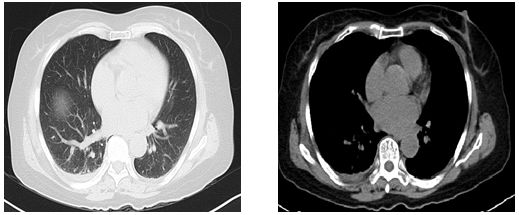

入院第4天双肺CT结果

提示:双肺间质改变,双侧胸腔积液

血气分析:氧分压65.8mmhg,氧饱和度90.9%,PH7.362